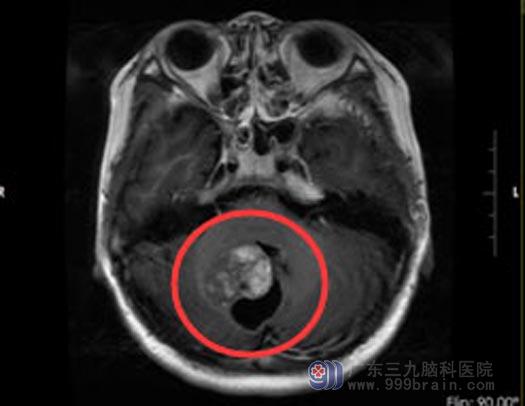

12岁的小陆,在学校与同学起争执,被对方打伤了头部。被打后去医院检查,令人没想到的是,脑部CT检查没有发现颅内受伤,却发现小脑有个不小的肿瘤:右侧小脑半球占位性病变。

小陆的父母吓坏了,赶紧来到广东三九脑科医院,结果提示:右侧小脑半球占位性病变,并右侧小脑半球轻度脑萎缩,考虑偏低级别肿瘤性病变,节细胞胶质瘤可能性大。综合神经外科鲁明主任建议手术切除肿瘤,考虑到小陆的年纪还小,肿瘤部位特殊,手术风险很大,决定先行放疗再进行手术,以减少术中的出血。

一个月的放疗结束后,由鲁明主任主刀进行了手术,显微镜下连同病变脑皮层一并切除,大小约2cm×2.5cm,手术很成功。术后经过半个月的康复,已经顺利出院,春节后可以正常回归校园了。

手术前